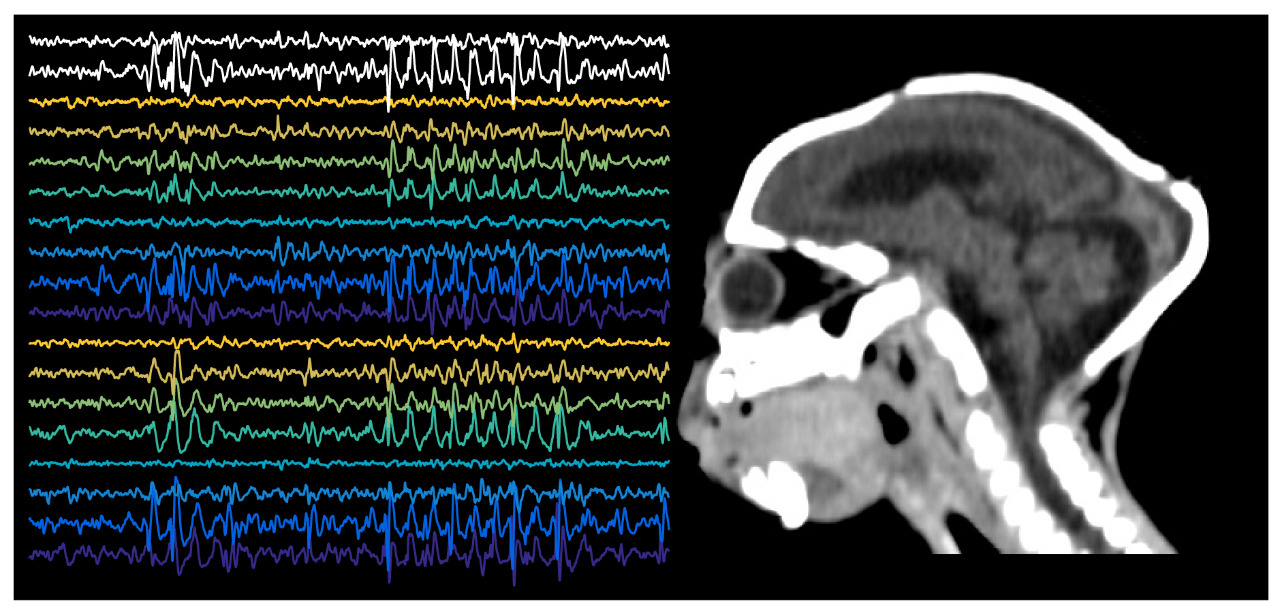

Também lá, conhecemos a neuropediatra, Dra. Áurea Nogueira de Melo. Áurea já estava coletando registros de eletroencefalografia (EEG) das crianças naquela época. Durante o exame de EEG, são colocados eletrodos presos com adesivo na pele da cabeça e este equipamento capta variações na atividade elétrica global que está acontecendo lá dentro, no cérebro. É como se estivéssemos ouvindo uma conversa atrás da parede, dá pra ouvir os sons, mas o que ouvimos é o somatório de todos os sons da sala. Não dá para distinguir quem entre as muitas pessoas está falando, ou se o aparelho de som está na frente ou atrás deles. Mas agora imaginem a dificuldade de fazer o registro de um recém-nascido ou criança pequena, a conversa já não é muito alta lá dentro, é um cérebro ainda se desenvolvendo. Fica ainda mais difícil se as paredes forem de uma casa pequena, como a cabeça destes pacientes. O objetivo desse registro então era saber o quão atrapalhada estava essa conversa dos neurônios. Mas apesar de todas estas dificuldades, os registros de Áurea e sua equipe são muito bons! Agora poderíamos analisar a função cerebral e compará-la a sua forma.

Claudio é acostumado a analisar sinais de registros com eletrodos dentro do cérebro. Mas os registros de EEG destas crianças eram um universo totalmente novo. Passamos longas horas aprendendo com Áurea sobre o que estávamos vendo. Ainda pedimos ajuda a Dra. Patricia Sousa, que é a especialista em EEG que atende as crianças do Maranhão, no projeto Ninar. Com toda essa informação em mãos, Claudio desenvolveu funções matemáticas para que o computador detecte automaticamente cada um dos sinais neurais que achávamos interessantes. Assim, conseguimos quantificar quando certas ondas apareciam e em quais crianças.

Dentre as ondas interessantes, estão as espículas. Estas ondas aparecem em pacientes com epilepsias. As epilepsias são grandes surtos de atividade cerebral descontrolada. Mesmo quando estão fora destes surtos, os pacientes apresentam espículas, e elas são mais facilmente vistas quando o paciente está dormindo. As crianças com microcefalia por zika apresentam espículas, mas não todas. E as crianças que apresentam espículas são exatamente aquelas que foram diagnosticadas com epilepsia no exame clínico com a Áurea. Isso por si é um fato intrigante. Por que umas crianças desenvolvem epilepsias e outras não? Será que umas tem mais espículas do que outras?

É aí que entra na história o Galtieri Medeiros. Galtieri é técnico em radiologia e trabalha junto com o Dr. Manuel operando a tomografia computadorizada e a ressonância magnética. Galtieri também é fera na análise das imagens e realizou a reconstrução tridimensional das regiões mais anterior do cérebro, o prosencéfalo, e das mais caudais, o tronco encefálico e o cerebelo (vejam no vídeo o prosencéfalo em vermelho, o tronco encefálico em azul e o cerebelo em amarelo). Cruzando estes dados com os do EEG, observamos que as crianças que apresentam ondas típicas de epilepsia, como as espículas, possuem um volume cerebral menor. E que quanto menor o seu cérebro mais anterior, o prosencéfalo, mais espículas elas apresentam. Assim, o grau da malformação causada pelo zika influencia o desenvolvimento de epilepsias e também a quantidade de ondas típicas deste transtorno.

Reconstrução tridimensional do cérebro feita a partir de exame de tomografia computadorizada